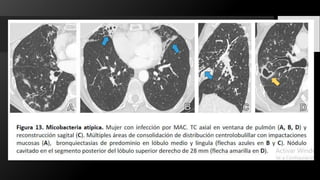

Las infecciones por micobacterias atípicas o micobacterias no tuberculosas (NTMB) son causadas por micobacterias

distintas de Mycobacterium tuberculosis . Se componen de decenas de organismos diferentes, los más comunes

son M. avium-intracelluare y M. kansaii .

Hay dos formas principales de presentación: clásica y no clásica.

La forma clásica se presenta como una enfermedad cavitaria en las zonas superiores de los lóbulos, con síntomas

similares a la tuberculosis pero sin hemoptisis. En las imágenes, hay nódulos en todos los lóbulos, con una ligera

predilección por los segmentos apical y posterior.

Los nódulos se convierten en cavidades, ya que también se producen nuevos nódulos. El grosor de la pared puede

variar desde una pared interior fina y lisa hasta una pared interior gruesa e irregular. Los nódulos cavitarios rara

vez superan los 2,5 cm de tamaño. Pueden verse pequeñas calcificaciones. Las adenopatías mediastínicas y los

derrames pleurales son raros .

La NTMB no clásica se presenta con tos crónica y como enfermedad bronquiectásica, con nódulos

centrolobulillares y patrón de árbol en brote en relación con las bronquiectasias. La cavitación y la linfadenopatía

mediastínica son raras en la NTMB no clásica